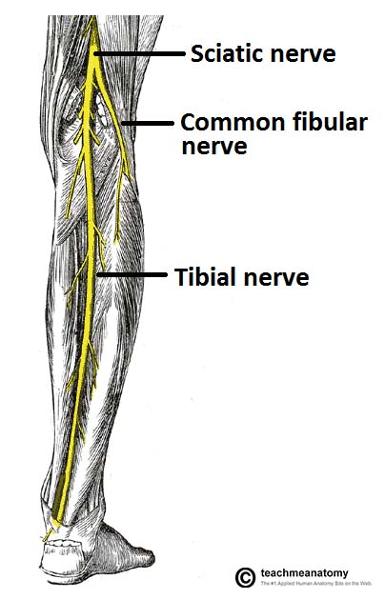

The sciatic nerve is formed from ventral rami from spinal cord levels ________-

L4 - S3

What is the path of the sciatic nerve?

exits the pelvis through the greater sciatic foramen. IN the posterior gluteal region, located inferior to piriformis m

Into which two nerves does the sciatic nerve bifurcate?

tibial and common fibular

The tibial nerve is fromed form ventral rami from spinal cord levels _______

L4-S3

The tibial nerve is the (medial/lateral) division of the sciatic nerve

medial

What is the pathway of the tibial nerve?

runs through popliteal fossa

runs with tom dick AN harry though medial malleoulus

bifurcates into medial and lateral plantar nerves

The common fibular nerve is formed from ventral rami from spinal cord levels _______

L4 - S2

The common fibular nerve is the (lateral/medial) division of the sciatic nerve

lateral

Describe the pathway of the common fibular nerve

wraps around the neck of the fibula

bifurcates into deep and superficial fibular nerves

What muscle does the common fibular division of sciatic nerve innervate?

ONLY biceps femoris short head

origin course and distribution of sciatic nerve

O L4-S3

C leaves pelvis through greater sciatic foramen inferior to piriformis; enters gluteal region; descends deep to biceps femoris; bifurcates into tibial and common fibular nerves at apex of popliteal fossa

D no muscles

O C D of common fibular nerve

O sciatic nerve

C forms as sciatic nerve bifurcates at apex of popliteal fossa. follows medial border of biceps femoris with its tendon. passes over posterior aspect of head of fibula then winds around neck of fibula deep into fibularis longus where it divides into deep and superficial fibular nerves

D knee joint via articular branch and lateral aspect of posterior leg via sural cutaneous nerve

(common fibular branch of sciatic nerve innervates short head of biceps femoris)